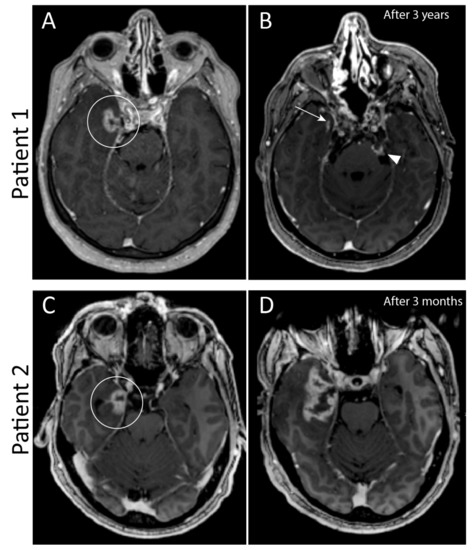

| Patient Number | Primary Tumour Location | Surgical Approaches | Postoperative Radiotherapy | Ectopic Recurrence Site | Time to First Ectopic Recurrence (Months) | Treatment of Recurrence |

|---|---|---|---|---|---|---|

| 1 | Clivus |

| Proton | 2x Ala major os sphenoid 2x Cutaneous nodules | 9 | Surgery Photon radiotherapy (Linac) |

| 2 | Craniocervical junction |

| Proton/Photon | Paravertebral paramedian right Neuroforamen C4-C5 right | 7 | Surgery Proton therapy |

| 3 | Craniocervical junction |

| Proton | Subcutaneous retroauricular Subcutaneous neck 3x Neck muscle left + right | 18 | Surgery Photon radiotherapy (Linac) |

| 4 | Clivus |

| Proton | Nose septum Subcutaneous nose | 147 | Surgery |

| 5 | Clivus |

| Proton / Photon | Ala minor os sphenoid Subcutaneous preauricular Frontal bone Subcutaneous frontal Dura mater frontal right | 41 | Surgery Photon radiotherapy (Linac) |

| Patient Number | Primary Tumour Dose (GyRBE) | Number of Fractions | Protocol | Regrowth of Primary Tumour after RT (Months) | Number of Ectopic Recurrences | First Ectopic Recurrence Area RT Dose (GyRBE) | Time Interval between Radiotherapy and First Ectopic Recurrence (Months) | Time Interval between First Surgery and RT (Months) |

|---|---|---|---|---|---|---|---|---|

| 1 | 74 | 37 | 54 GyRBE + 20 GyRBE boost | 9 | 4 | 54 | 9 | 5 |

| 2 | 78 | 39 | 56 GyRBE proton + 20 Gy photon boost | No regrowth of primary tumor | 2 | 1 | 22 | 18 |

| 3 | 74 | 41 | Standard skull base chordoma protocol | 37 | 5 | 50 | 24 | 24 |

| 4 | 74 | 37 | 54 GyRBE + 20 GyRBE boost | No regrowth of primary tumor | 2 | 1 | 98 | 23 |

| 5 | 68 | 34 | 48 GyRBE proton + 20 Gy photon Boost | No regrowth of primary tumor | 5 | 1 | 43 | 5 |

| Average | 74 | 37.6 | 39 | 3 | 21 | 41 | 17 |